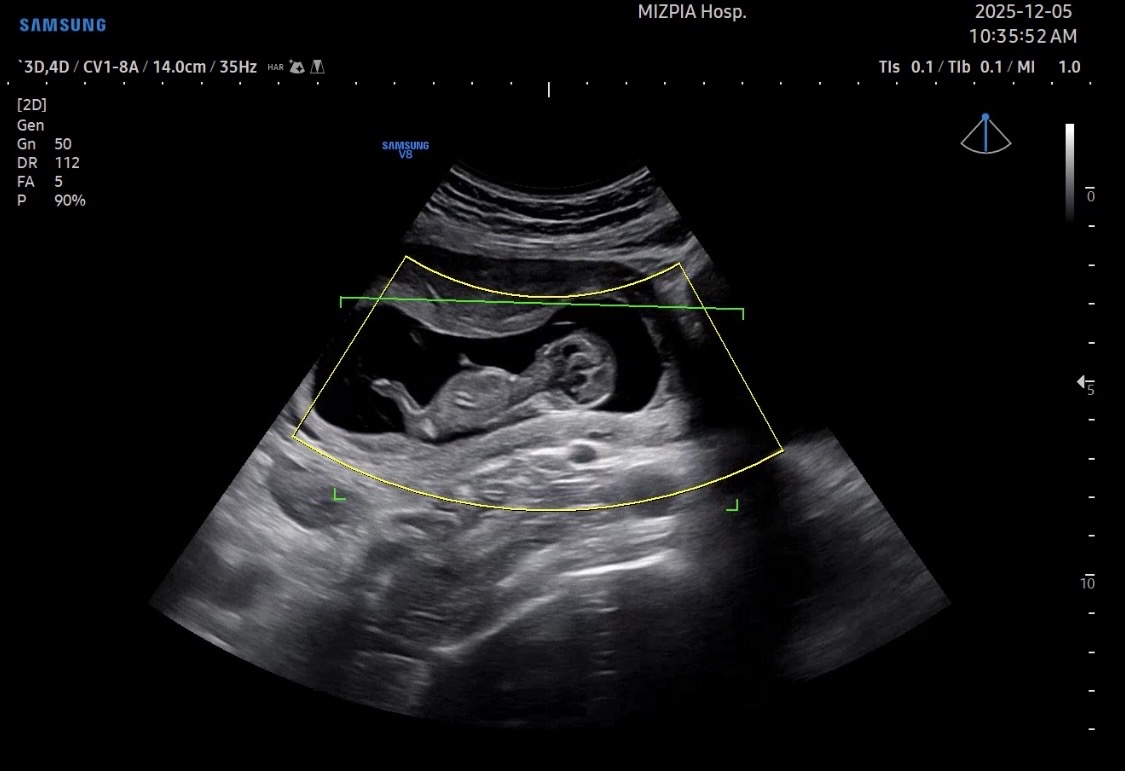

각도법 봐주세요🙇🏻♀️

첫째는 아들이고 이건 둘째 초음파 사진이에요 지금 아들이 정말 사랑스럽고 건강하게만 자라주면 바랄게 없고 이렇게 사랑스러운 아가가 또 태어날 수 있을까 싶게 정말 예쁘고 행복해요😍 저는 아들이 또 있어도 첫째 같은 아들이라면 언제든 환영인데 남편은 딸을 엄청 원하고 있어서 제가 자꾸 아들이라고 희망 갖지 말라고 하고 있는 중입니다! 저는 각도법 봐도 잘 모르겠더라구요ㅠㅠ 혹시 아시는분들은 어떻게 보이시나요???